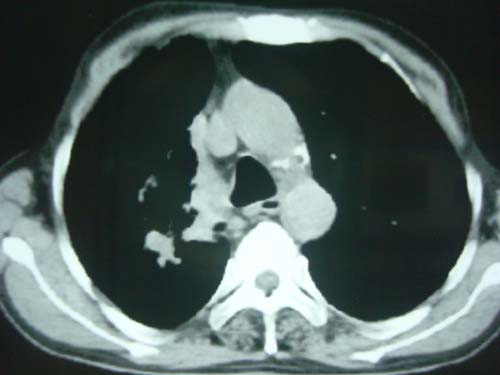

男性,45岁,胸疼,低热,抗炎治疗后症状缓解拍片检查发现左上肺有高密度灶,考虑结核,做ct示条件有限采集了部分图像,图像质量差请谅解

右上肺结核,左上肺周围型肺癌可能性大

尘肺

问下职业史,矽肺结节也说不定。